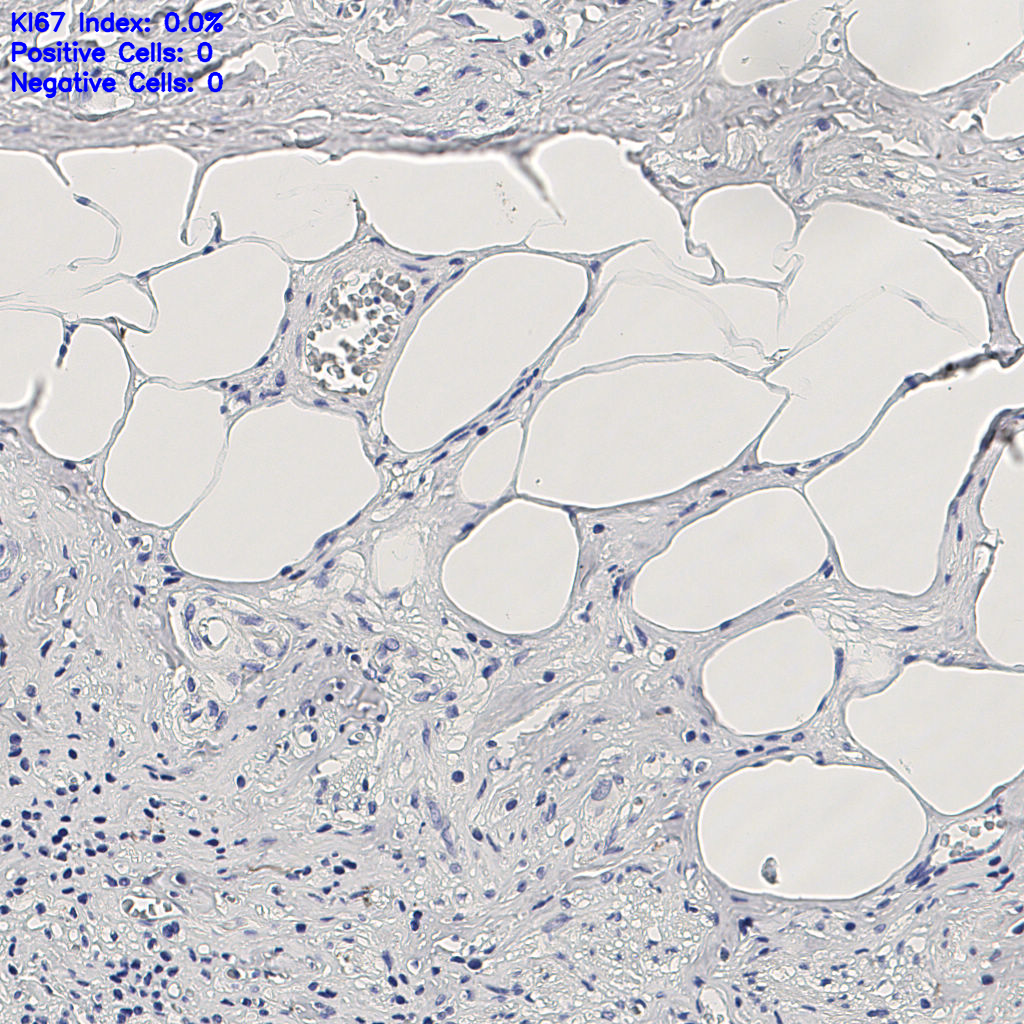

7.85%

Ki67 指数

阴 1104 阳 94

slice_9_22_x8064_y19712.png

slice_9_22_x8064_...